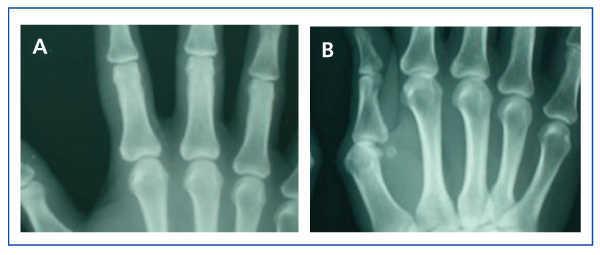

In January 2006, she presented serious SPTH, with notable increase in iPTH levels. The parathyroid ultrasound revealed an echo-rich pseudo-nodular structure in the posteriomedial area of the left thyroid lobe, compatible with parathyroid gland hypertrophy. A series of X-rays showed signs of hyperparathyroidism in the bones of both hands and wrists, with VC in radial and interdigital arteries. The mammography revealed multiple linear VC in both breasts (Figures: 1A, 2A, 3A and 4A; hand and mammary gland images in 2006).

During this period, the X-ray series showed that the interdigital artery calcifications had disappeared, and the bone appeared better structured (Figures 1B and 2B; hand X-ray, 2007). The mammography also showed regression of the VC. Initial linear calcifications were replaced by irregular calcifications (Figures 3B and 4B; mammary glands in 2007).

Figure 1. (A) Anteroposterior X-ray of left hand in 2006. (B) Anteroposterior X-ray of left hand in 2007

Figure 2. (A) Anteroposterior X-ray of right hand in 2006. (B) Anteroposterior X-ray of right hand in 2007